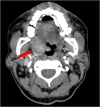

Talaromyces marneffei is an opportunistic fungal infection seen in immunocompromised patients including those with HIV/AIDS. It is usually seen in patients who live in or are from tropical Asia. In HIV patients, oropharyngeal and laryngeal lesions are usually part of disseminated infection. We describe a case of 63-year-old Vietnamese male with history of HIV/AIDS who presented with localized T. marneffei tonsillar infection without disseminated disease. Imaging studies showed a right tonsillar mass with right cervical lymphadenopathy which was initially thought to be malignancy. The patient underwent biopsy of the mass and histology showed noncaseating granulomas on hematoxylin and eosin stain as well as yeast on Grocott methenamine silver stain. Fungal culture of the biopsy specimen grew suede-like grayish-white colonies with diffuse underlying deep red color pigment which was identified as Talaromyces marneffei. The patient was treated with intravenous liposomal amphotericin B and achieved resolution of symptoms and tonsillar mass. In HIV/AIDS patients who are either from endemic regions or with history of travel to endemic areas particularly Southeast Asia and China, T. marneffei infection should be considered in differential diagnoses of a tonsillar mass.